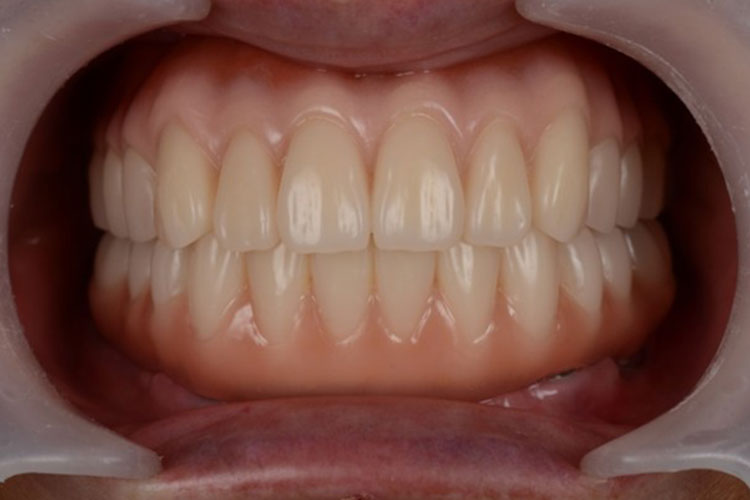

All-on-4症例 Case1

Treatment cases

Before

After

インプラント治療は、咀嚼機能の改善だけでなく、 口腔周囲筋の発達により見た目の若返りにも貢献してくれます。